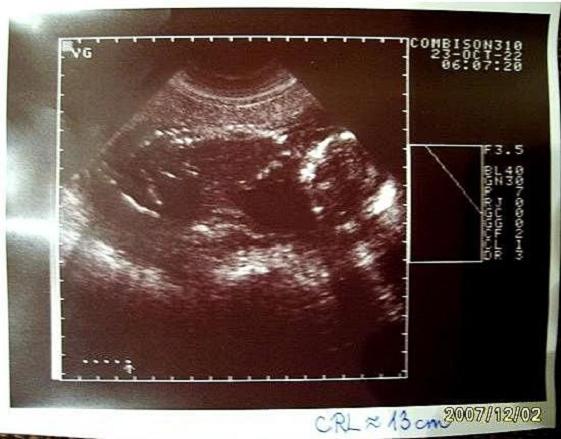

18+5 Babakifli - CRL: 13 cm (07/10/09)